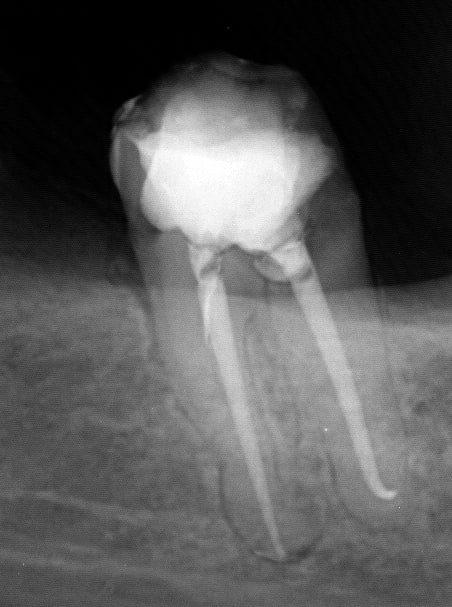

Endo de ce matin :

--

Endo 3  2  c nes txljrd - Eugenol

Endo 3  3  fin a4y8gs - Eugenol